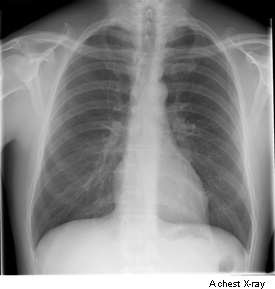

An x-ray is a test that uses small amounts of radiation to take pictures of the inside of your body. They are a good way to look at bones and they can show changes caused by cancer or other medical conditions. X-rays can also show changes in other organs, such as the lungs.

Image by credit test.